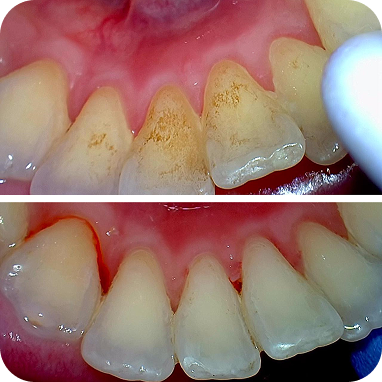

Setiap scaling dilengkapi polishing, membuat gigi lebih halus, bersih, dan tampak cerah setelah perawatan.

Karang gigi dibersihkan menyeluruh, termasuk area sulit dijangkau, sehingga gigi dan gusi tetap sehat lebih lama.

Hilangkan noda membandel akibat kopi, teh, atau rokok. Gigi tampak lebih bersih dan cerah

Di Dharmawangsa Dental Studio, scaling sudah termasuk polishing. Hasilnya lebih bersih menyeluruh, bukan sekadar karang gigi terangkat. Jangan tergiur harga murah di luar yang berakhir dengan biaya tambahan.